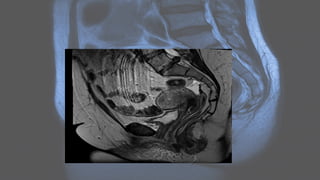

On MRI

• MRI displays the zonal anatomy of the uterus. The myometrial layers

are indistinguishable on T1 imaging. It can be divided into three zones

on T2 weighted imaging7

:

• high T2 signal of endometrium

• low T2 signal of inner myometrium, known as the junctional zone

• intermediate T2 signal of the outer myometrium .

On MRI • MRIdisplays the zonal anatomy of the uterus. The myometrial layers are indistinguishable on T1 imaging. It can be divided into three zones on T2 weighted imaging7 : • high T2 signal of endometrium • low T2 signal of inner myometrium, known as the junctional zone • intermediate T2 signal of the outer myometrium .